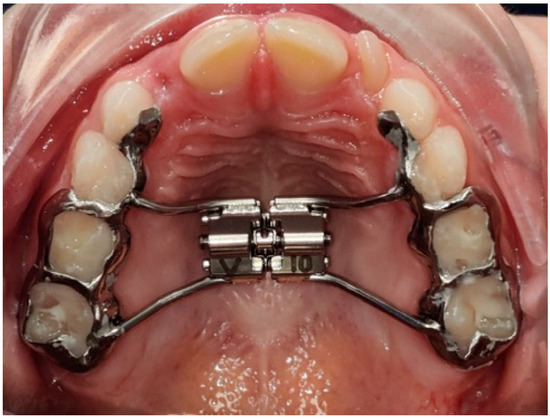

- Graf, S.; Vasudavan, S.; Wilmes, B. CAD-CAM design and 3-dimensional printing of mini-implant retained orthodontic appliances. Am. J. Orthod. Dentofac. Orthop. 2018, 154, 877–882. [Google Scholar] [CrossRef] [PubMed] [Green Version]

| Co-Cr | Crowns, implants, partial dentures, hyrax, lingual arch, transpalatal arch, retainers | High density (Co-Cr: 10 g/cm3; Titanium: 4.5 g/cm3), hardness (Vickers hardness Co-Cr: 550–800 MPa; Vickers hardness Titanium: 830–3420 MPa) and elastic modulus higher than bone structures (Co-Cr: 220 GPa; Titanium: 110 GPa; Cortical bone: 18–20 GPa; Trabecular bone: 10–14 GPa). Biocompatible and implantable materials available in SLM/EBM machines. |